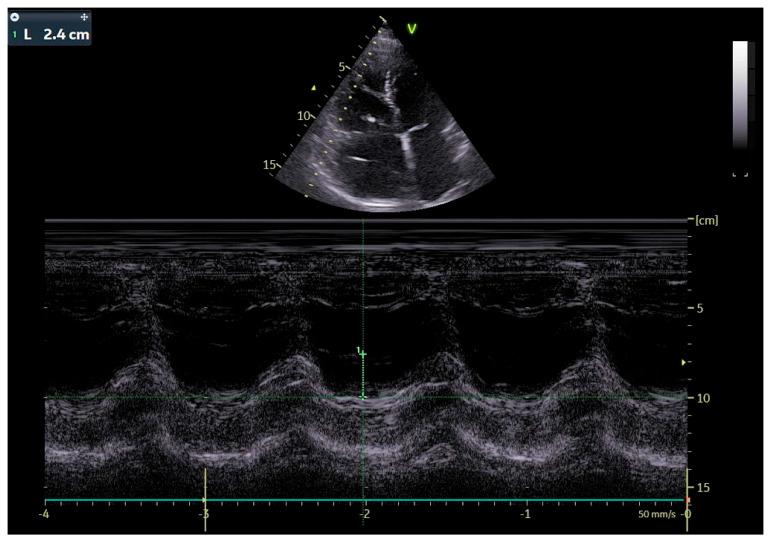

Cardiological and oncological patients comprise the majority of patients admitted to the emergency unit with chronic or acute conditions that are the dominant cause of death worldwide. However, electrotherapy and implantable devices (pacemakers and cardioverters) improve the prognosis of cardiological patients. We present the case report of a patient who, in the past, had a pacemaker implanted due to symptomatic sick sinus syndrome (SSS) without removing the two remaining leads. Echocardiography revealed severe tricuspid valve regurgitation. The tricuspid valve septal cusp was in a restricting position due to the two ventricular leads passing through the valve. A few years later, she was diagnosed with breast cancer. We present a 65-year-old female admitted to the department due to right ventricular failure. The patient manifested symptoms of right heart failure, predominated by ascites and lower extremity edema, despite increasing doses of diuretics. The patient underwent a mastectomy two years ago due to breast cancer and was qualified for thorax radiotherapy. A new pacemaker system was implanted in the right subclavian area as the pacemaker generator occupied the radiotherapy field. In the case of right ventricular lead removal and the need for pacing and resynchronization therapy, guidelines allow a coronary sinus for LV pacing to avoid passing the leads through the tricuspid valve. We facilitated this approach in our patient, suggesting that the percentage of ventricular pacing was very low.

心脏病患者和肿瘤患者占因慢性或急性疾病入住急诊科患者的大多数,这些疾病是全球主要的死亡原因。然而,电疗法和植入式设备(起搏器和心脏复律器)可改善心脏病患者的预后。我们报告一例患者,该患者过去因症状性病态窦房结综合征(SSS)植入了起搏器,但未取出剩余的两根导线。超声心动图显示严重三尖瓣反流。由于两根心室导线穿过瓣膜,三尖瓣隔叶处于受限位置。几年后,她被诊断出患有乳腺癌。我们介绍一名65岁女性因右心室衰竭入住该科室。尽管利尿剂剂量不断增加,但患者仍表现出以腹水和下肢水肿为主的右心衰竭症状。该患者两年前因乳腺癌接受了乳房切除术,并符合胸部放疗条件。由于起搏器发生器占据放疗区域,在右锁骨下区域植入了新的起搏器系统。在需要移除右心室导线并进行起搏和再同步治疗的情况下,指南允许通过冠状窦进行左心室起搏,以避免导线穿过三尖瓣。我们在患者中采用了这种方法,表明心室起搏的百分比非常低。